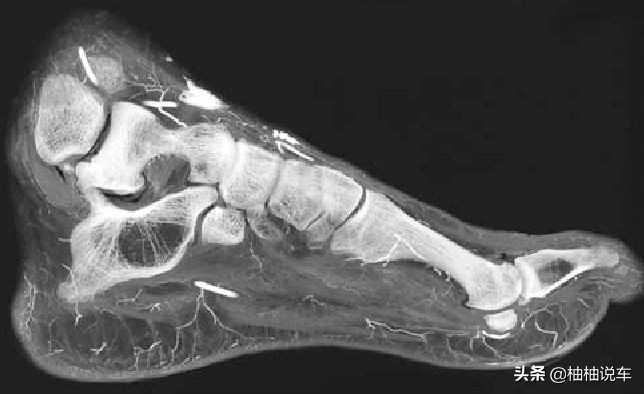

这位网友是位小姐姐,在周末出门,刚好下雨穿的是凉鞋,脚面裸露在外面,在路口的地方,被一辆私家车压到,被压到的一瞬间没有感觉到疼痛,但还是觉得脚要废掉了,要变成了瘸子了。等车轮压过,整个脚面有一大块伤口,混着下雨的泥水,看着有点惨烈,感觉到的就是脚面表皮疼,骨头没感觉。到达医院拍片子后,确认骨头没事,然后就是消毒,站起来久了,就会感觉脚比较胀痛。那希望网友C的小姐姐能够健健康复的恢复好哦。